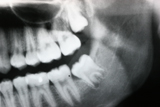

Wisdom Tooth Removal

Sometimes wisdom teeth are not functional, but instead create swelling and pain in the surrounding soft tissue, and they need to be taken out.

During the development of wisdom teeth, they often push away their neighboring teeth and contribute to anterior teeth crowding. Therefore, extraction of wisdom teeth is recommended in their early stage of eruption to prevent anterior crowding. The stress of eruption of wisdom teeth that grow horizontally causes dental decay on the 2nd molars and extraction is recommended before dental decay initiates.

Before / After